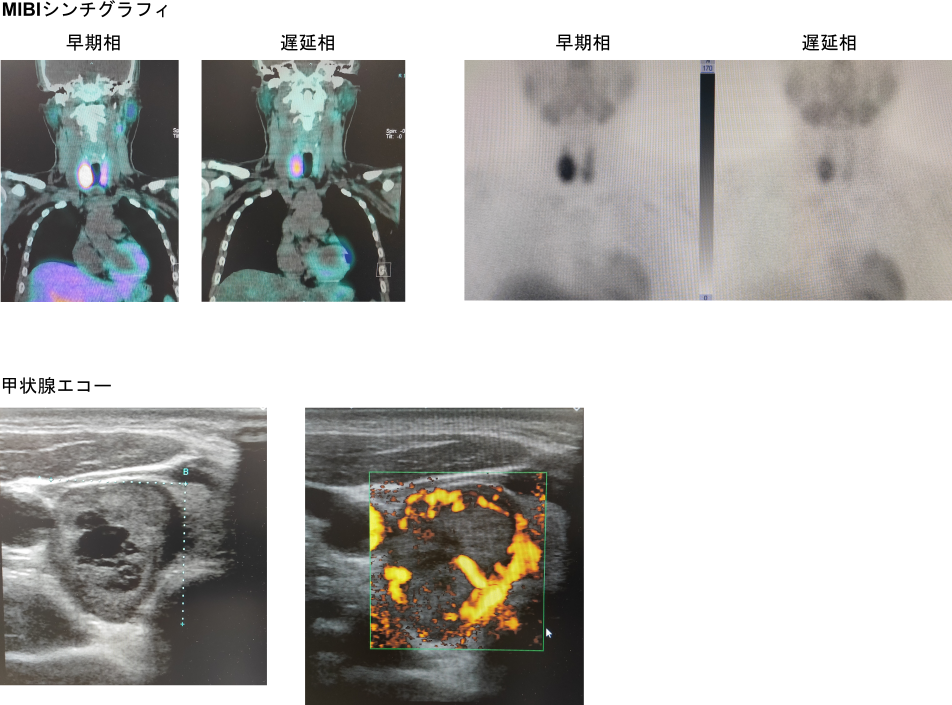

〇症例281

# 原発性副甲状腺機能亢進症

<検査所見>

補正Ca 13.8, PTH 403.8

<画像所見>